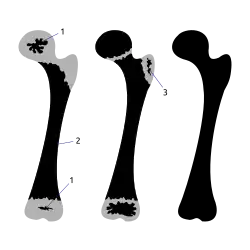

Апо́физ (apophysis, PNA, BNA; от греч. αποφυσις, отросток) — возникший из самостоятельного ядра окостенения отросток кости вблизи эпифиза. Как правило, функция апофизов заключается в прикреплении к ним мышц.

Апофизы окостеневают энхондрально из заложенных в их хряще центров окостенения и построены из губчатого вещества[1]. Так, например, у человека плечевая кость имеет три пункта окостенения в верхнем конце: эпифиз в головке и два апофиза в большом и малом буграх и четыре пункта в нижнем: два из них образуют эпифиз и два — апофизы, образующие внутренний и наружный мыщелки. Эти центры окостенения появляются на 3-м году жизни в большом бугре, на 5-м году — в малом и на 8-м — в обоих мыщелках. Объединение костной ткани апофизов с эпифизом происходит не одновременно: на 5-м году жизни присоединяется большой бугор, малый бугор сразу присоединяется сразу после образования, на 11-м году наружный мыщелок сливается с головчатым возвышением и на 18-м году к нижнему эпифизу прирастает внутренний мыщелок и в то же время нижний эпифиз сливается с телом кости ( верхний эпифиз прирастает на 20-м году жизни)[2].

Образование верхнего конца бедра происходит аналогично плечу. В нижнем конце на 4-м году возникает апофиз в большом вертеле и на 14—15-м году — в малом вертеле. Возникшие последними апофизы на нижнем конце бедра прирастают, наоборот, первыми на 17—18-м годах жизни человека[2].